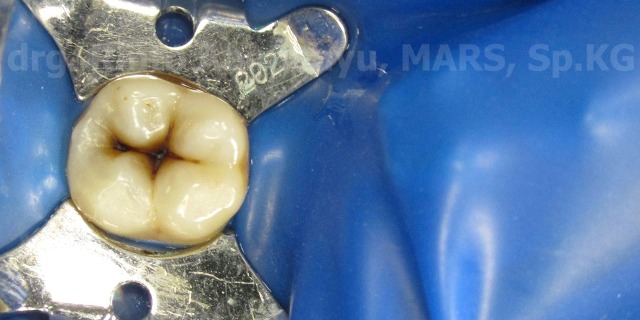

Isolasi dilakukan pada gigi itu menggunakan rubber dam..

Jaringan karies dibuang menggunakan bur carbide low speed, sampai terlihat jaringan yang sehat..

Nah setelah dipreparasi gigi sekarang siap untuk direstorasi… Pertama-tama dilakukan etsa, tehnik yang saya pakai adalah selective etch yaitu hanya mengetsa pada bagian email saja, hal ini salah satunya adalah untuk menghindari terjadinya post restorative sensitivity… dibilas dengan air, keringkan, kemudian diaplikasikan bonding generasi ke 7 pada email dan dentin, diulas merata keseluruh permukan kavitas kurang lebih selama 20 detik, dan disinar…

Setelah itu untuk lapisan awal saya menggunakan komposit flow tipis untuk mengakomodir shrinkage stress yang terjadi akibat C-Factor yang besar pada kavitas site 1 ( kelas I)… Dilanjutkan dengan komposit pasta, untuk lapisan bawah menggunakan komposit Z350 XT (3M) warna A3 Body selanjutnya memakai Z 350 XT (3M) warna A2 Body untuk luarnya…